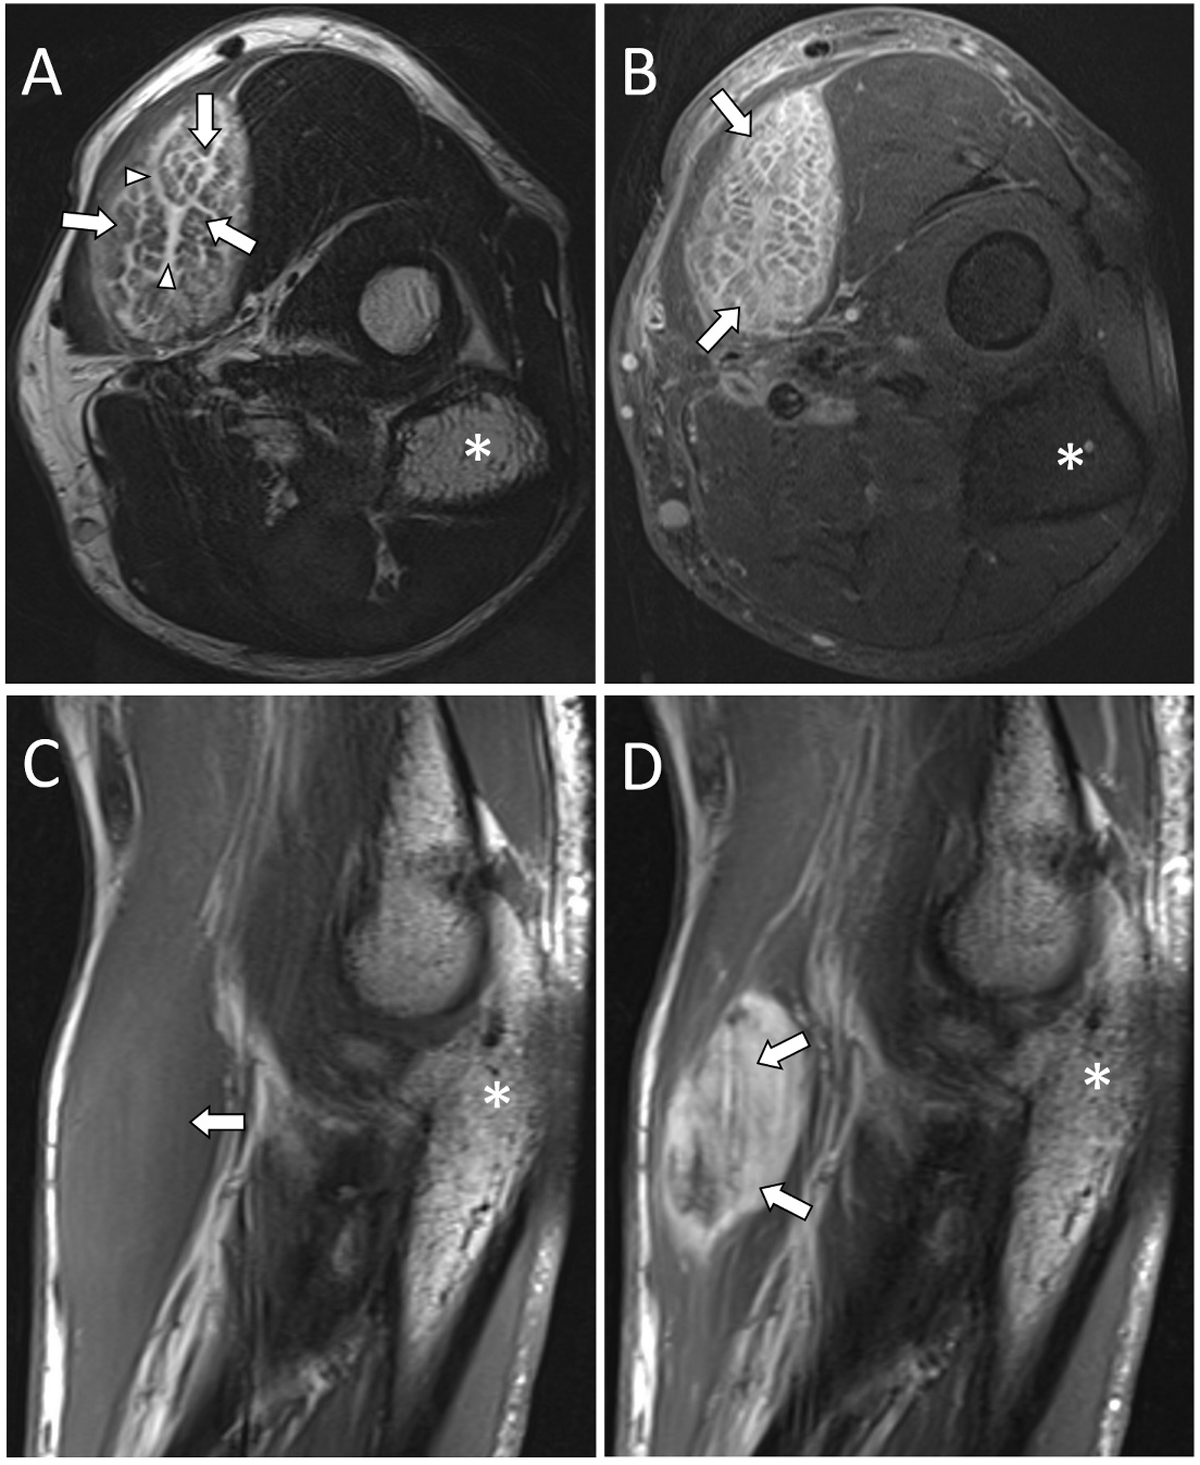

Figure 3

MRI images of PM in the left brachioradialis muscle. Axial T2WI (A), axial post-contrast T1WI fat-saturated (B), sagittal T1WI (C), and sagittal post-contrast T1WI (D) images demonstrate a T2 hyperintense lesion with a marked enhancement. The T2WI (A) shows hyperintense bands (white arrowheads) interspersed with intact muscle fibers (white arrows). Olecranon (*).